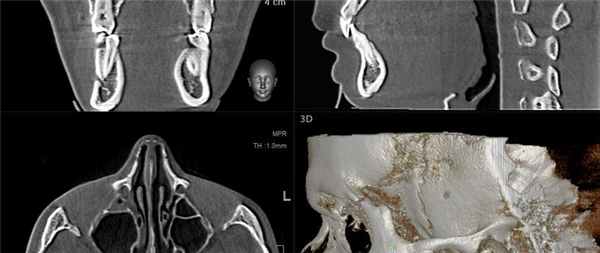

На аксиальной КЛКТ на уровне мыщелков ВНЧС их длинная ось находится под углом, т.к. медиальный полюс расположен сзади. При реформатировании необходимо корректировать изображения в сагиттальной и корональной косых плоскостях, что важно для точного воспроизведения. На косой сагиттальной КЛКТ правого ВНЧС определяется, что мыщелковый отросток и ямка имеют нормальную морфологию и правильное пространственное положение. Кортикальные пластинки шейки мыщелка суживаются по направлению к заднему и переднему верхним контурам мыщелка, на вершине мыщелка кортикальный слой (субхондральная кость) достигает толщины яичной скорлупы. Передний контур мыщелка и задний контур возвышения образуют неконгруэнтный сустав. На корональной косой КЛКТ нормального мыщелка определяется, что нарушения морфологии мыщелка и ямки отсутствуют, пространственные отношения между этими двумя структурами не изменены. Контуры мыщелка, в целом, соответствуют контурам ямки, суставное пространство имеет равномерную ширину. На первой из трех косых сагиттальных КТ ВНЧС (снаружи-кнутри) визуализируется передний гребень, формирующий передний край суставной поверхности мыщелка. Пневматизация крыши суставной ямки и возвышенности является нормой. На срезе через среднюю часть ВНЧС визуализируются костные компоненты сустава, имеющие нормальную морфологию. Задний скат должен иметь округлую форму с умеренно закругленным гребнем. Субхондральная кость возвышения в норме толще, чем у мыщелка. На срезе изнутри от мыщелка визуализируются каменисто-барабанная щель, среднее ухо и слуховые косточки, расположенные близко друг к другу. Шиловидный отросток височной кости, который может иметь различную длину и толщину, находится изнутри и сзади от суставной ямки. Шилососцевидное отверстие, из которого в височную кость выходит лицевой нерв (ЧМН VII), визуализируется позади суставной ямки.